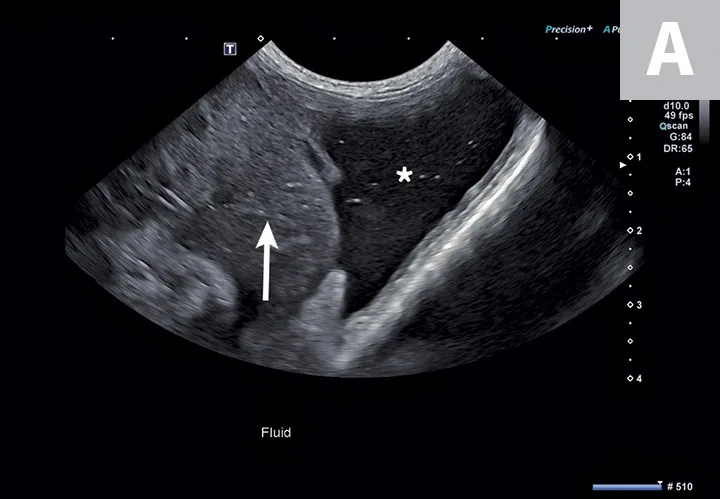

FIGURE 2

Abdominal effusion (A; asterisk) adjacent to a normal spleen (arrow). Abdominal carcinomatosis with secondary neoplastic effusion was diagnosed. Left parasternal short-axis view of a heart with pericardial (B; asterisks) and pleural effusion (arrow).